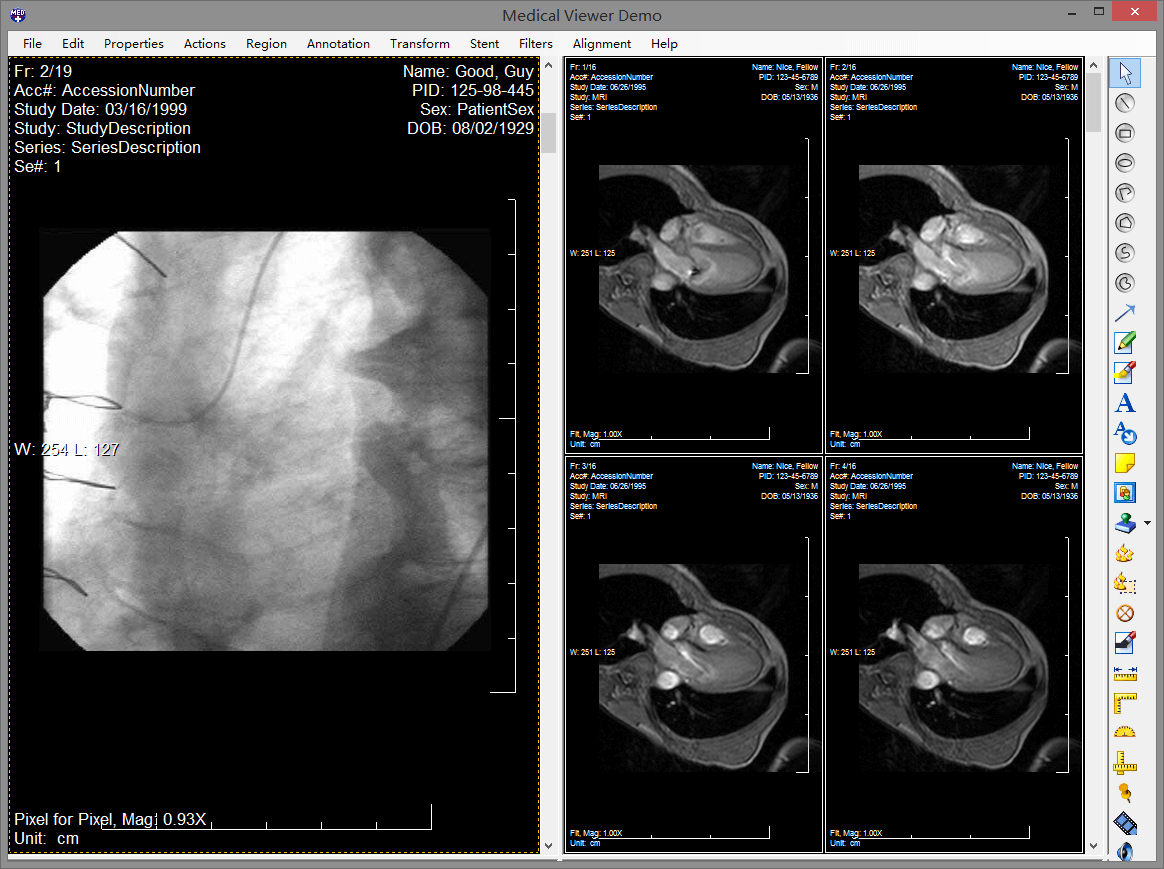

leadtools pacs能够使开发人员非常容易的开发一整套完整的pacs解决方案,组建企业级pacs服务器和客户端,实现dicom通信、查询、存储dicom影像数据。leadtools拥有成熟的pacs框架,您只需要修改logo就可以轻松构建一整套pacs系统。它包含了全套的权限、服务、存储、客户端、html5 web 端,而这一切都是基于多年大型医院需求的总结体现,并且已经完整的在超过150家医院真正部署。

leadtools 能够使您快速创建高质量、全功能和安全的基于web的医学影像工作站,您可以在上面查看3d图像、标注、测量、灰度等等。完全不需要部署任何的客户端,实现零空间占用。这样您就可以轻松的在iphone、ipad、android和windows phone上随时随地查看病人信息。一次开发,跨平台使用,您再也不必头疼需要为医院开发不同客户端了,只需要html5 web端就可以全平台浏览器支持。